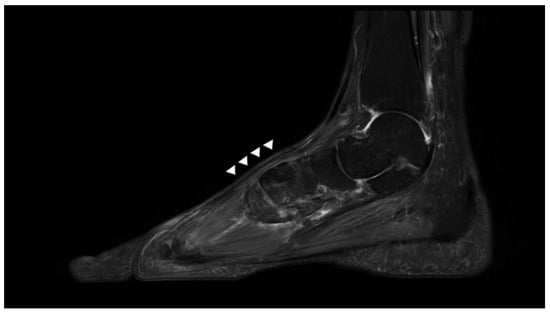

2.1. Preoperative Evaluation